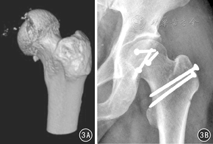

髋关节脱位合并股骨头骨折是髋关节常见创伤之一,既往采用牵引复位、后侧入路的切开复位均有较高的股骨头坏死率。急诊条件下,经SHD行股骨头骨折切开复位、清理髋关节内碎屑、处理髋臼后壁、复位固定股骨头骨折片,股骨头血运得到最大限度地保护,创伤性关节炎和股骨头坏死率降至最低水平。见图3。